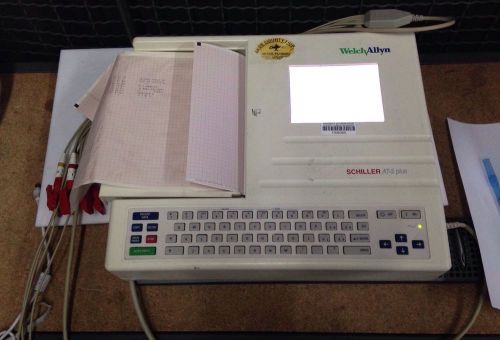

Welch Allyn Schiller AT-2 Plus EKG ECG Electrocardiograph Machine w/ Cables